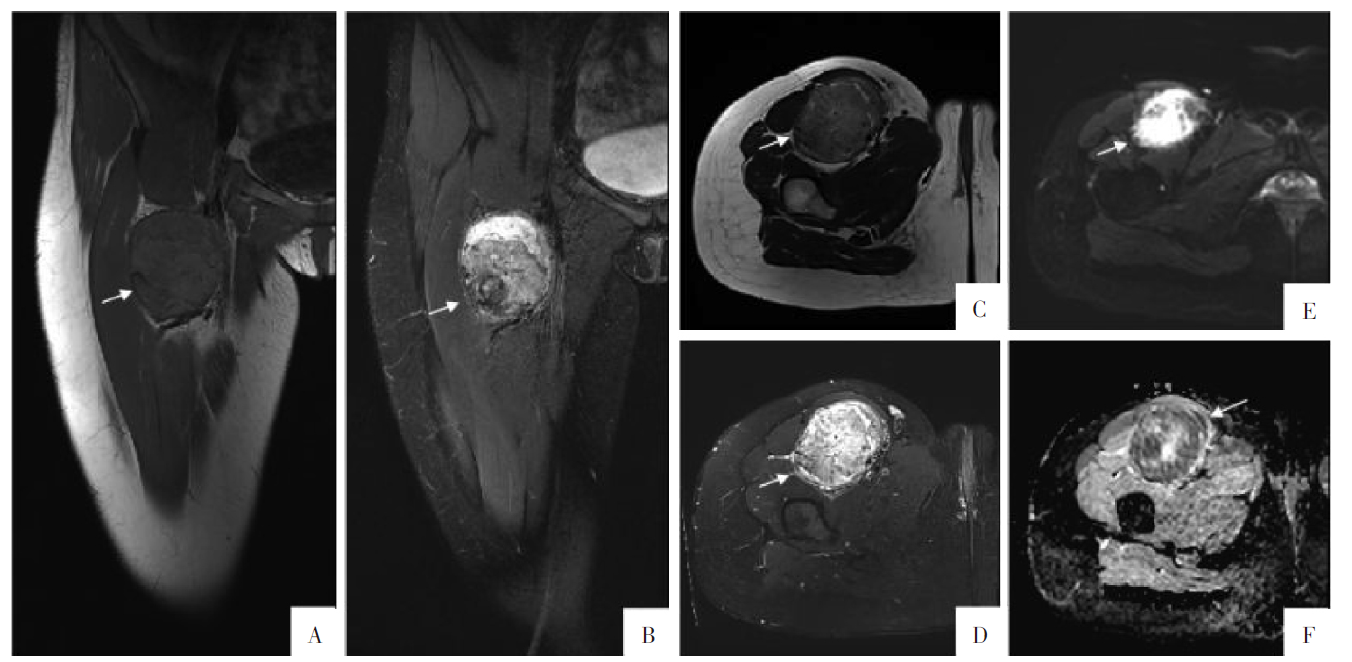

图4

病人女,23岁,右下肢软组织恶性PEComa,伴

TFE3

重排。A—F图分别为冠状面T

1

WI、T

2

WI-FS,横断面T

WI-FS、DWI、ADC图。可见大腿前内侧肌间隙内团块状异常信号,T

WI上呈等信号,T

WI-FS呈不均匀高信号,DWI呈部分高信号,ADC图呈低信号;肿块大小约5.9 cm×7.0 cm×7.4 cm,邻近的缝匠肌、股直肌及髂腰肌均受推挤,但无侵袭表现。